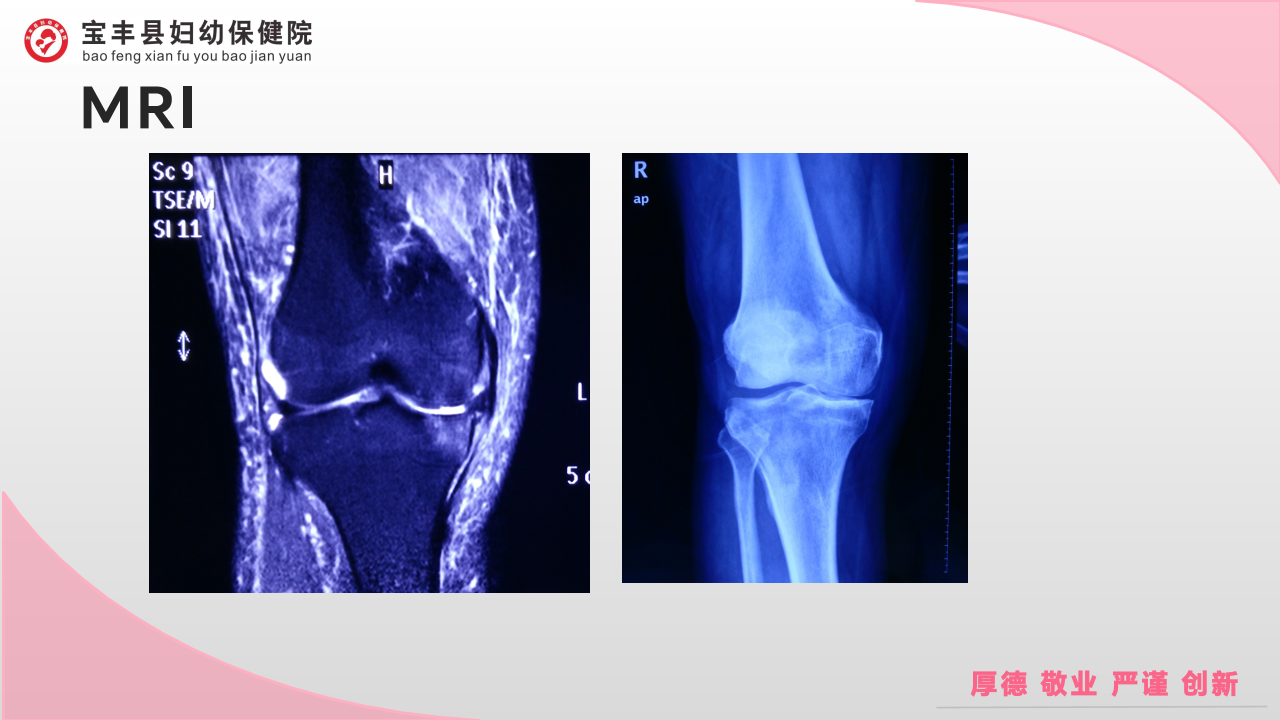

膝骨性关节炎的阶梯治疗